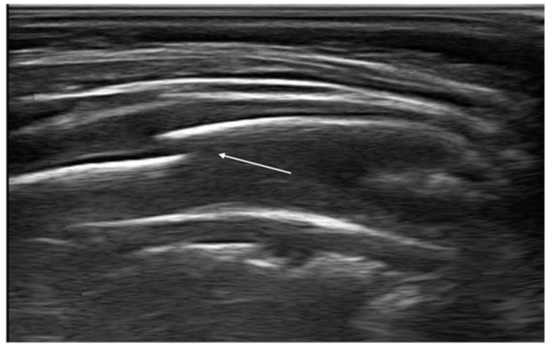

In addition, recent evidence has shown that ultrasounds may be a useful tool for the detection of bone fractures, in particular rib fractures [80]. A rib fracture is diagnosed when a discontinuity of the cortical alignment is observed as a clear disruption of the anterior echogenic margin of the rib (Figure 13). Furthermore, in the case of previous fractures, it is possible to observe at the ultrasound the bone callus that determines an irregular cortical profile different from that of the adjacent ribs. Rib fractures are suspected in pediatric age; in fact, they represent indicators of child abuse. Therefore, thoracic ultrasound could be helpful in identifying, promptly, children at risk of abuse, reducing the exposure to ionizing radiation [81,82].

Figure 13.

Rib fracture in transverse scan along the major axis of the rib (white arrow).